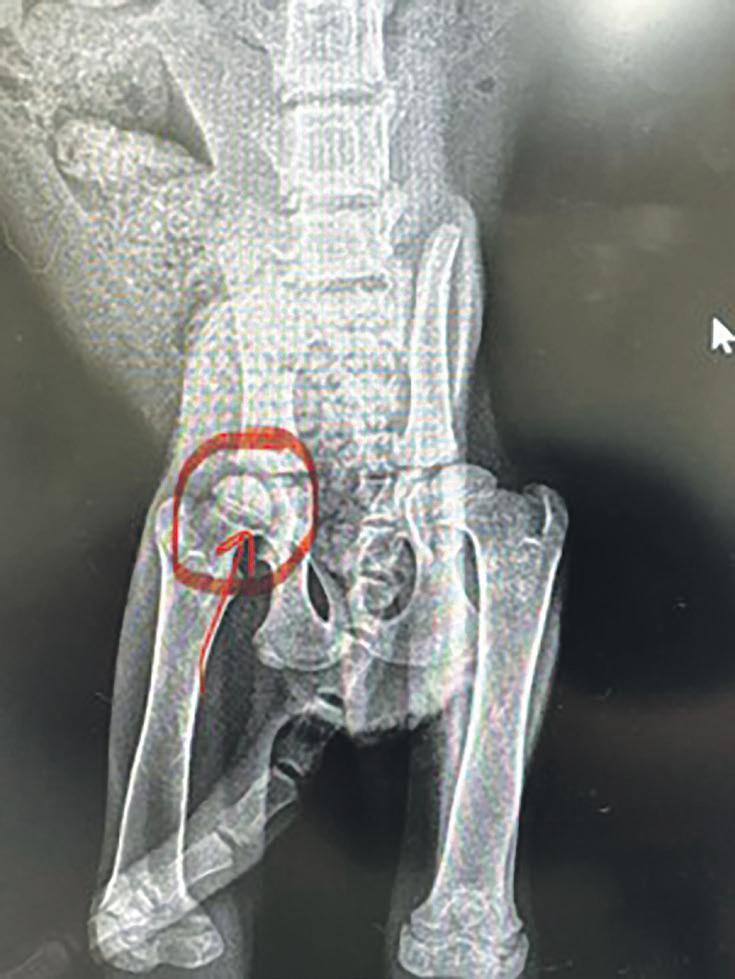

Please, Hero needs our help!

Life has not been fair or kind to our young kitten we named ‘Hero’.

Hero was brought into the refuge after being found abandoned under an empty house, skin covering bones, bloated belly and very unwell.

This led to a trip to the vet

where Hero was so unwell she couldn’t even hold her head up.

Dr Tiana was quick into action giving Hero a blood transfusion, fluids and bringing her temperature up.

Hero gained a lot of strength and had the spirit to live.

Once stabilised at her foster home it was discovered Hero was limping.

Another trip to the vet, an x-ray and we have now discovered Hero needs surgery for a fractured femoral neck through the growth plate.

The recommended surgery is a femoral head and neck ostectomy, with surgery Hero should live a pain free and normal life.

Hero’s surgery is going to be up to $1258.24.

We need to right the wrong that Hero has been

dealt with in her short young life.

If you’d like to donate towards our little Hero’s vet bill, please donate to